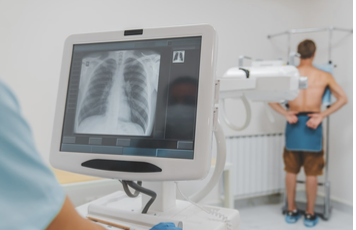

Why is a chest X-ray the most common procedure for diagnosing or suspecting SCLC?

A patient with or suspected of having SCLC would normally undergo a chest X-ray (CXR) before other imaging modalities are considered.

The reason CXR is commonly used is due to:

- Their low cost

- Easy accessibility

- Minimal radiation exposure, with a single CXR involving a dose of approximately 0.02 mSv (Bradley et al., 2019; Public Health England, 2008).

- While the radiation dose from a single CXR is minimal, repeated X-rays over time can add up.

- This is especially important for SCLC patients, who often require frequent imaging, such as PET (discussed later on), to track the progression of the disease and the effectiveness of treatment.

- Thus, the combined exposure over time can increase the risk of long-term side effects, such as a slightly higher chance of developing other cancers later in life.

- However, this risk is generally small compared to the immediate benefits of accurately diagnosing and treating SCLC.

Figure 1. A patient prepared for a chest X-ray (Laguna Beach Urgent Care, 2025).